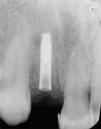

En los hallazgos radiográficos se apreció resorción radicular externa en la zona del cuello del diente y anquilosis (Figura 3).